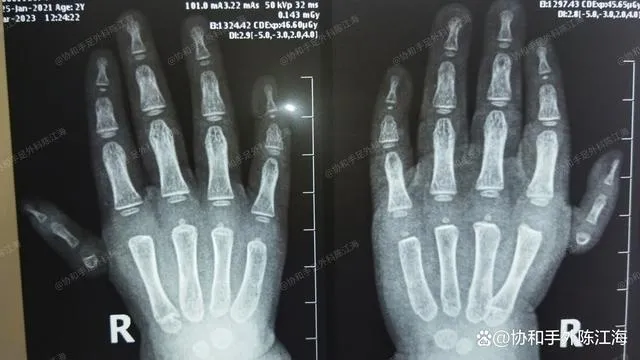

Raio X pré-operatório

Os pais tinham preocupações sobre o impacto potencial do transplante parcial do osso metacarpal na mão. Na realidade, qualquer tipo de cirurgia tem vários graus de impacto.